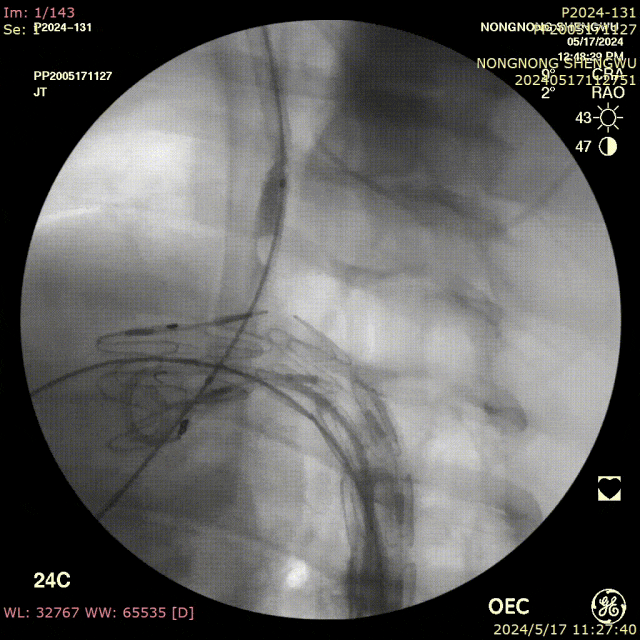

具体操作分两种模式:

预置模式:

先将器械送入主动脉,在目标分支开口处预张开前盘;

轻微回拉,使盘片卡住分支开口边缘;

再释放主体覆膜支架;

最后通过内置破膜针垂直穿透覆膜支架,完成开窗。

在主动脉内张开,轻轻牵张,使其卡在分支开口

后顶模式:

先释放主体覆膜支架;

将长鞘顶住支架,推送器械使其前盘在主动脉内张开并向后牵拉,同样实现锚定于分支开口;

再行破膜。

输送器顶住覆膜支架,张开后向后牵拉卡住分支开口